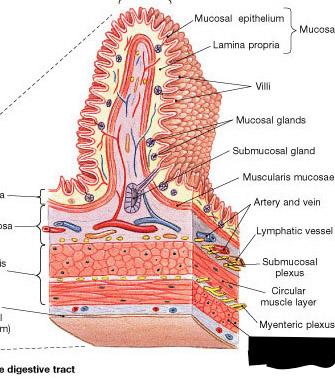

Goblet cells

Inner circular layer (of muscular externa)

Lacteal

Lumen

Microvillus (s.) Microvilli (pl.)

Mucosa

Outer longitudinal layer (of muscular externa)

Serosa

Submuscosa

Villus (s.) Villi (pl.)